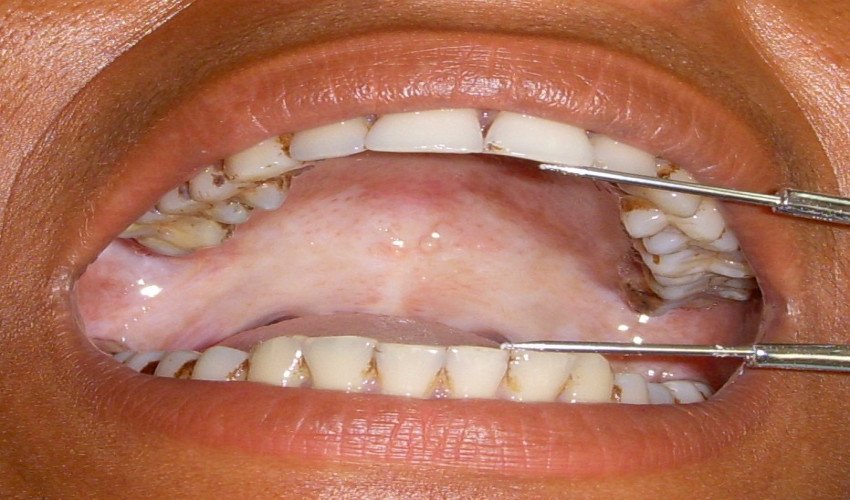

Cavities, gingivitis, periodontitis, candidiasis, oral ulcers, herpes infections are some of the common diseases with which the patient reports in dental college. Oral cancer is one of the most common cancers in the world. It is a preventable disease & its risk factors are very well known Dentistry, in particular, plays an important role in treating them.

Association of Candida with Potentially Malignant Oral Lesions

Prevalence of potentially malignant disorder in relation to adverse habits in patients attending a dental college in Lucknow (UP)